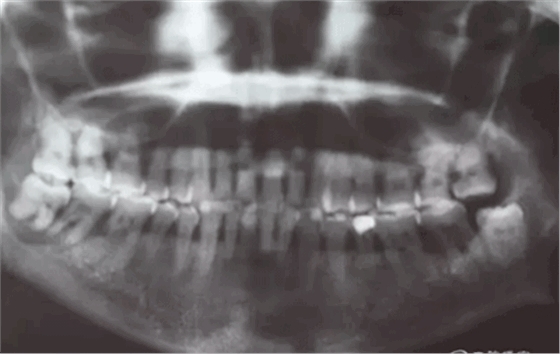

患者,白xx,女,40歲。主訴:右側(cè)下后牙牙探針齦反復(fù)腫痛,不能吃東西數(shù)月。??茩z查:48松動(dòng)Ⅲ,47松動(dòng)Ⅱ,牙周探針:48牙周袋均8mm,47遠(yuǎn)中牙周袋8mm,x全景片檢查:48牙槽骨弧形吸收至根尖區(qū),陰影較大。47遠(yuǎn)中牙槽骨吸收至遠(yuǎn)中根尖部,近中牙槽骨部分角形吸收。診斷:拔除48,試保留47.同期實(shí)行47牙周刮治術(shù)。患者同意治療方案,簽知情同意書。

圖2.局部的放大影像情況。48骨質(zhì)吸收至下頜管邊緣,陰影范圍廣,拔除48后牙槽窩處理要小心。